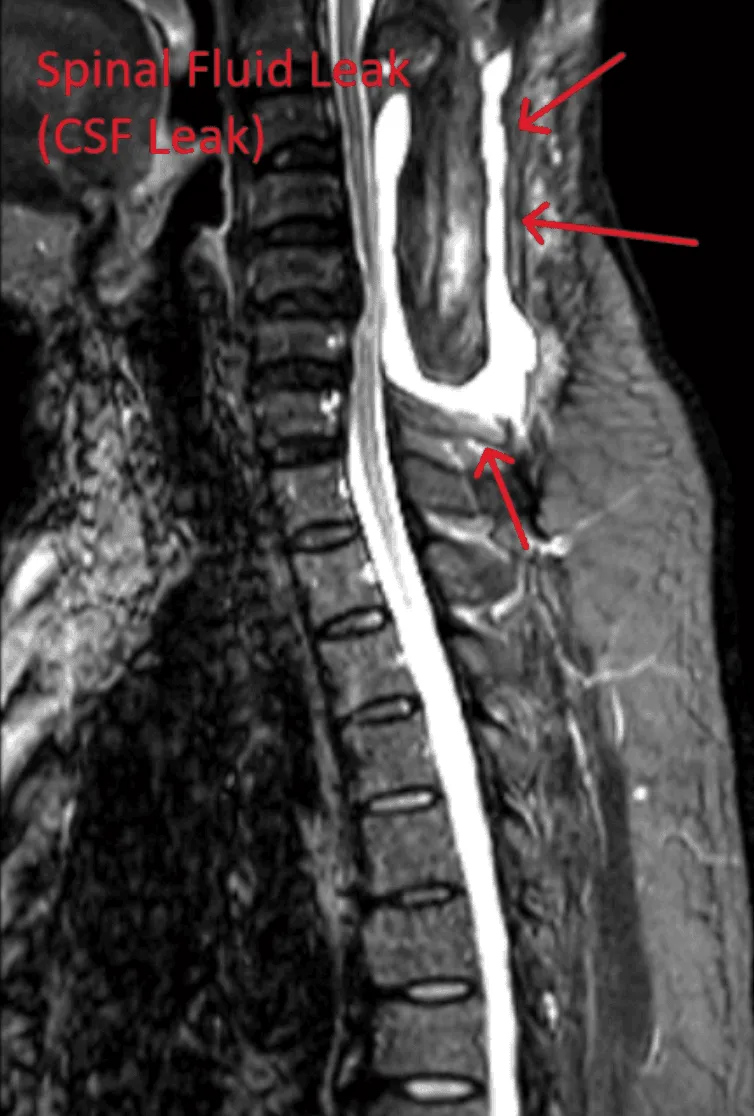

MRI showing a spinal fluid leak with arrows indicating the affected area.

Spinal Fluid Leak

Dural tears can occur, causing cerebrospinal fluid leakage.